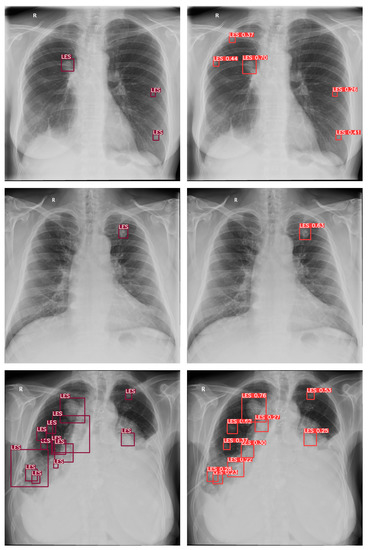

3.1. Software

3.1.2. Model Architecture

3.4. Assessment

4. Results